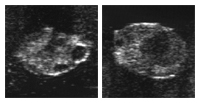

Le corps jaune (corpus luteum) produit l’hormone de la gestation (progestérone). Cette hormone conduit, via la circulation sanguine, à des modifications dans le comportement et au niveau de l’appareil génital. On appelle aussi le jeune corps jaune corpus haemorrhagicum. Celui-ci est mou et de couleur rouge. D’un corps jaune mûr au milieu du cycle, on dit aussi qu’il est en fleur. Il est souvent en forme de bouchon de champagne. Il devrait atteindre une part d’au moins 50% de l’ovaire.

Il est possible que, durant la phase du corps jaune, 1 à 2 follicule(s) grandisse(nt) sur l’ovare. On parle alors de vague folliculaire et de follicules intermédiaires. Ces follicules meurent sans qu’il y ait d’ovulation. Le corps jaune ne se résorbe que lorsque de la prostaglandine est fabriquée par l’utérus non gravide.